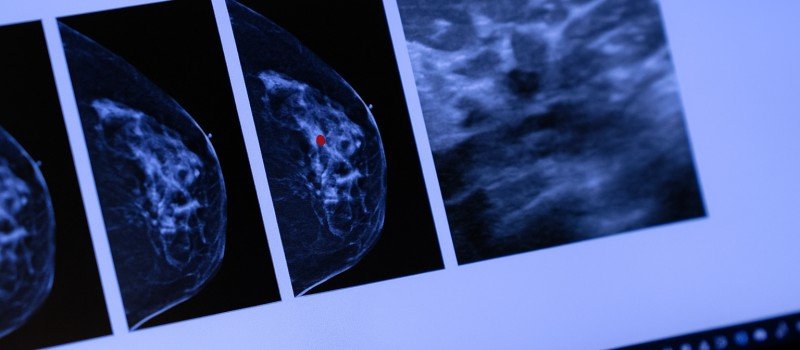

A cutting-edge AI-ML model is turning routine mammograms into a powerful tool to predict women’s risk of heart disease. Developed by The George Institute for Global Health in collaboration with the University of New South Wales and University of Sydney, the model uses mammographic images and age alone to forecast major cardiac events, matching the accuracy of traditional risk calculators that rely on multiple clinical measurements.

Trained on 49,000 mammograms from women in metropolitan and rural Victoria, Australia, and linked to hospital and mortality records, the AI model identifies subtle patterns that may escape human observation. Yet, many women are underdiagnosed and undertreated, as heart disease is often mistakenly seen as a male-dominated condition.

The new model could change that. By integrating cardiovascular risk screening into mammography- a test millions of women already undergo, the system offers a “two-for-one” approach, detecting both breast cancer and heart disease risk simultaneously. Unlike earlier studies that relied primarily on breast arterial calcification, this AI tool analyzes a broader range of mammographic features, making it more accurate across all age groups and easier to implement without additional patient data.